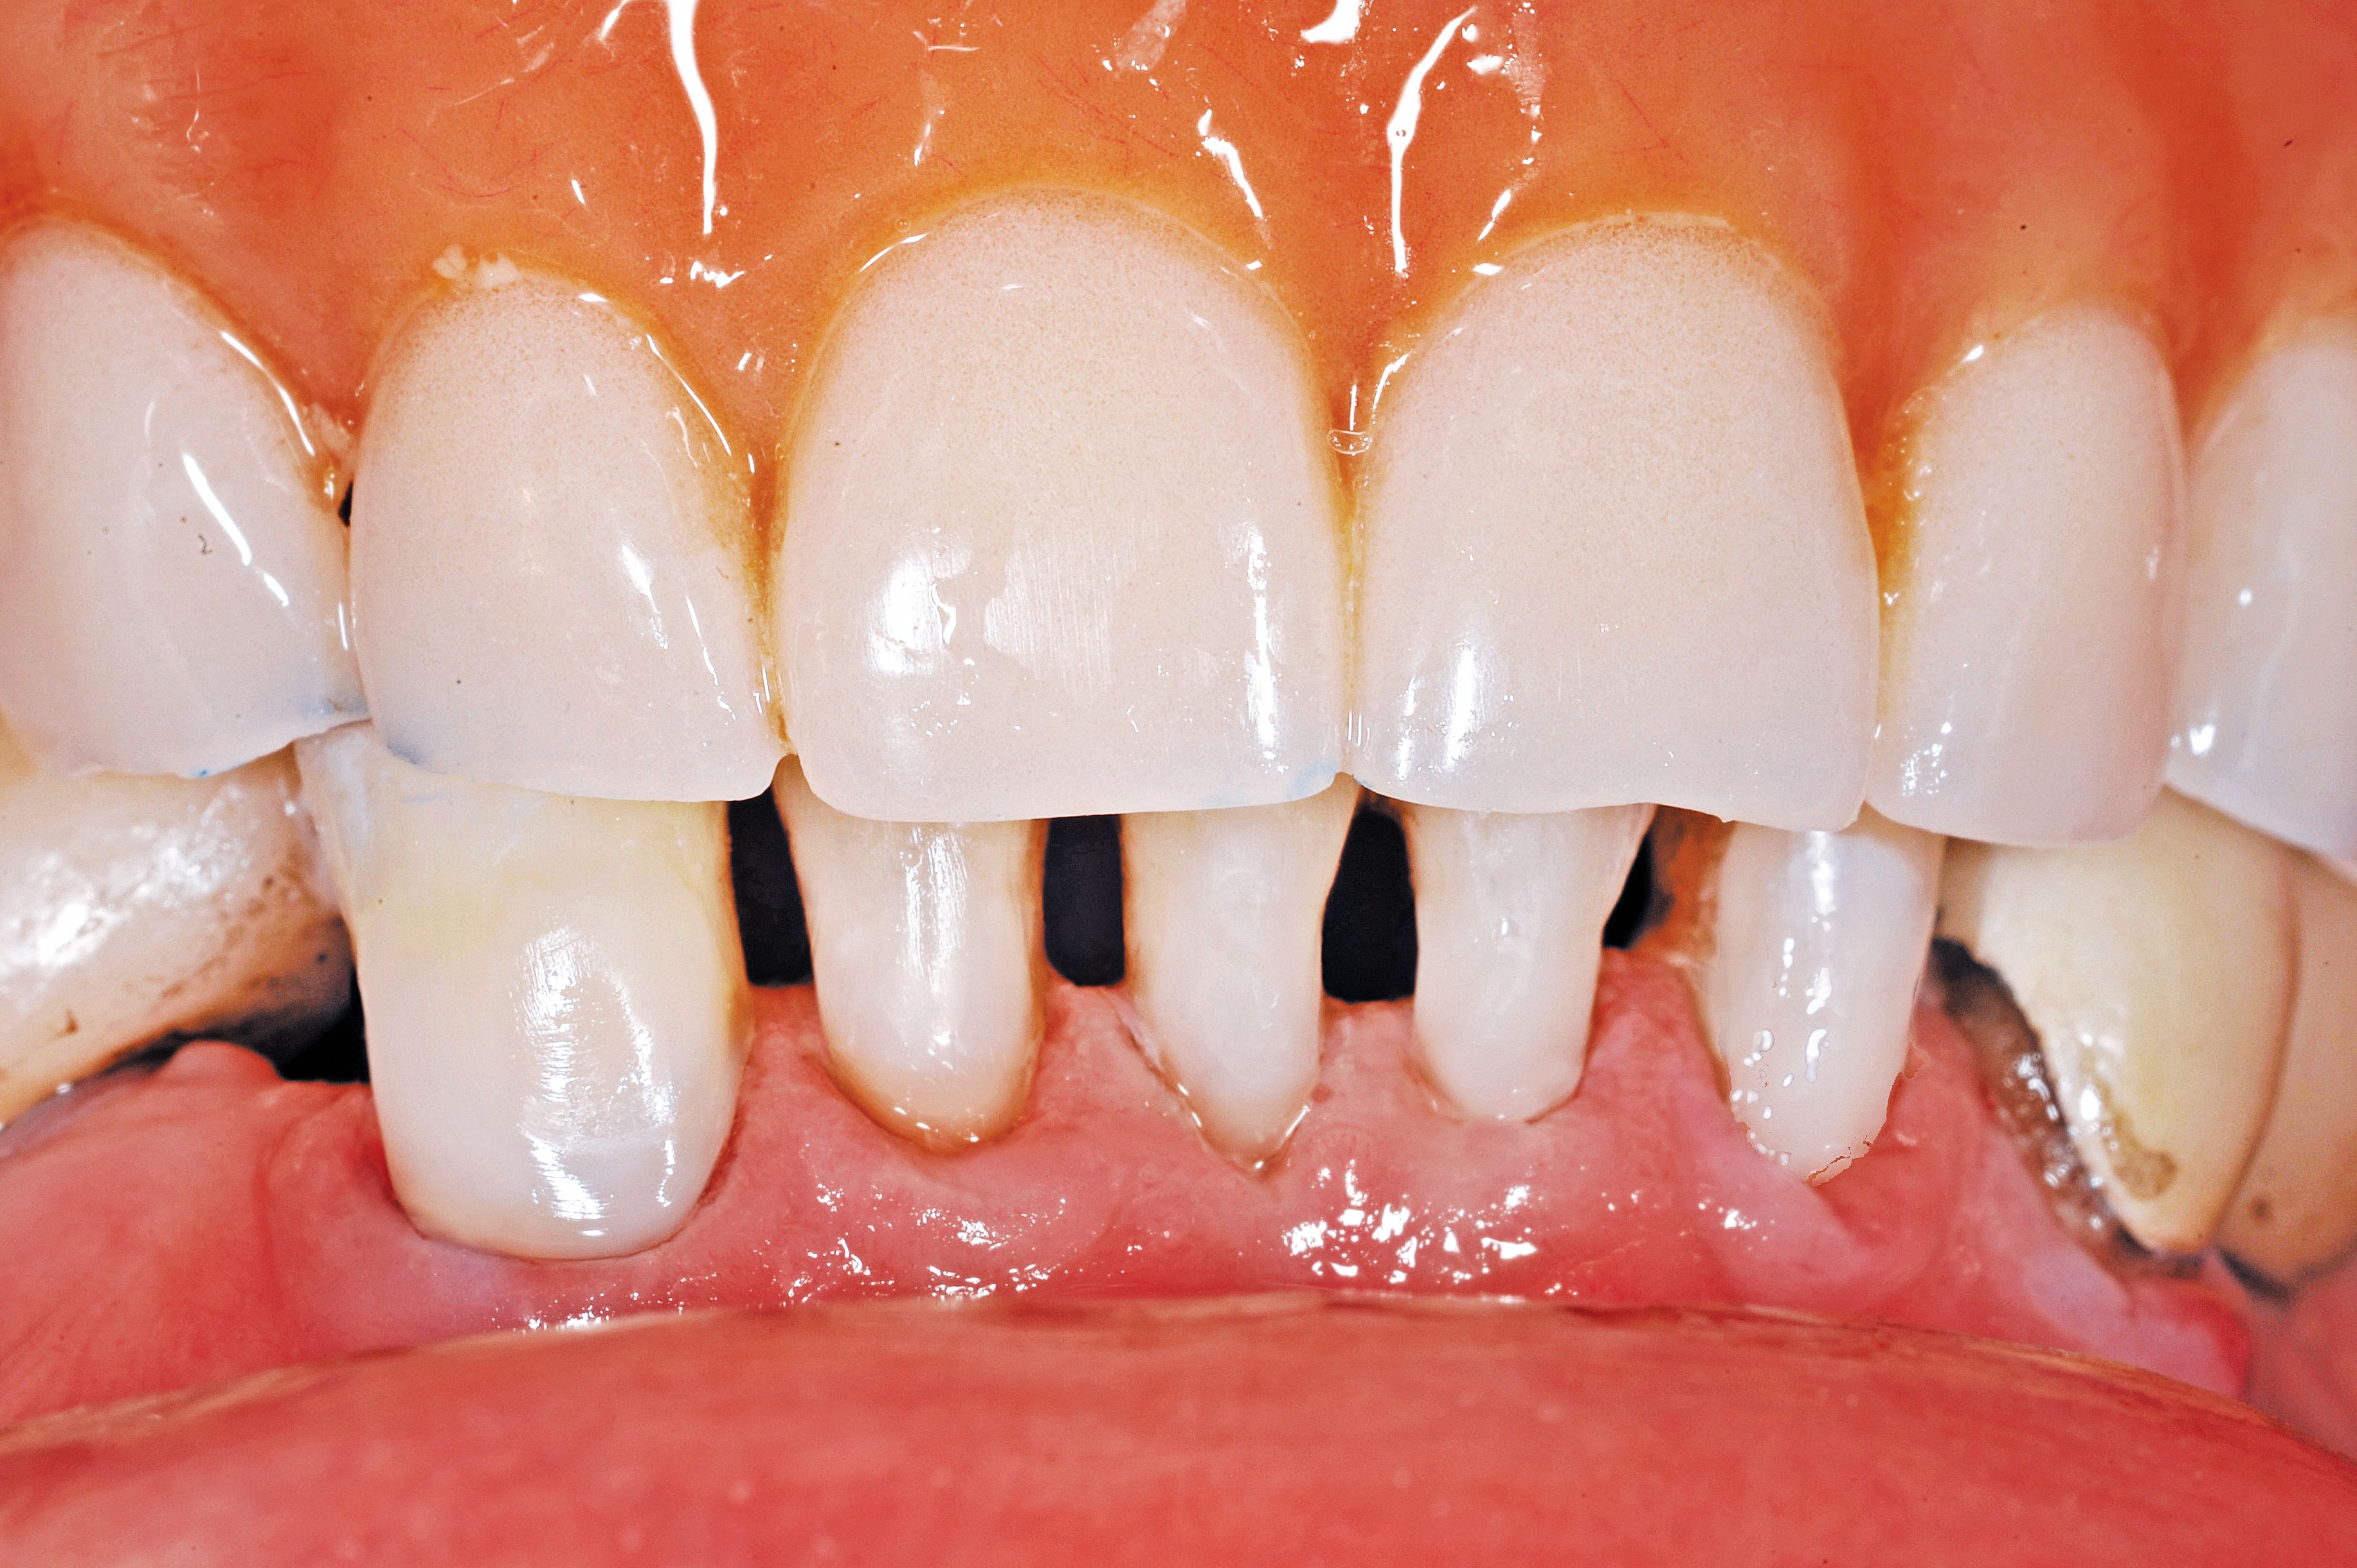

Fig. 3

Dentin and cementum surfaces that are exposed to the oral environment are not easily bonded. Contaminants such as chemicals, foods, fluoride and medications decrease the bondability of these surfaces unless they are prepared. Instead of using a bur and more aggressive dentin removal, the exposed dentin surfaces were air abraded using 50 micron aluminum oxide until frosty (Fig. 3).

A MicroEtcher (Danville Engineering) was used to clean the dentin surface, remove the outer layer and provide micromechanical retention. The goal was not to remove healthy tooth structure as would be done if retention grooves were cut with a handpiece and bur but instead to change the surface area and prepare it for more successful adhesion.